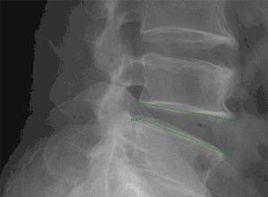

(2)牽引性骨刺(tractionspur):此種骨刺一般多位於椎體前方或側方,呈水平方向突起,基底部距椎間盤外緣約1mm。這是由於,腰椎不穩時相鄰椎體出現異常活動,使椎間盤纖維環的外層纖維受到牽張性勞損所致。其臨床意義也不同於常見的爪形骨刺。小的牽張性骨刺意味著有腰椎不穩存在,而大的牽張性骨刺僅提示該節段曾經有過不穩。當腰椎重新獲得穩定後,牽張性骨刺可逐漸消失(圖2)。